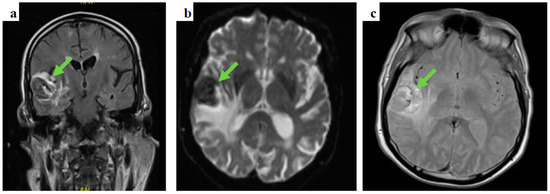

The left groin core biopsy showed mostly necrosis with a few surviving cells of metastatic malignant melanoma, with overexpression of S100 and MelanA, but negative for AE1/3, CK18, P63, CD45, and CD30 (Figure 4).

Figure 4.

Melanoma cells (numerous dark circle-like cells, melan A staining) on the left groin core biopsy.

This patient presented with seizures and the brain MRI findings were consistent with metastatic malignancy. There was no evidence of cutaneous melanoma primarily noted on clinical examination, and the CT-CAP was not able to demonstrate the primary, highlighting some of the limitations of standard imaging techniques. FDG PET findings raised the suspicion of colorectal origin at the anorectal junction and the patient was referred to the colorectal multidisciplinary team meeting based on the most common aetiology for that location and pattern of spread, causing delay in addressing the melanoma primary, with the conclusive diagnosis later revealed by biopsy. This again illustrates the limitations of imaging alone in this condition, and the key role of histology and, particularly, immunohistochemistry, given that a substantial proportion of ARMMs have an amelanotic appearance even microscopically [14].